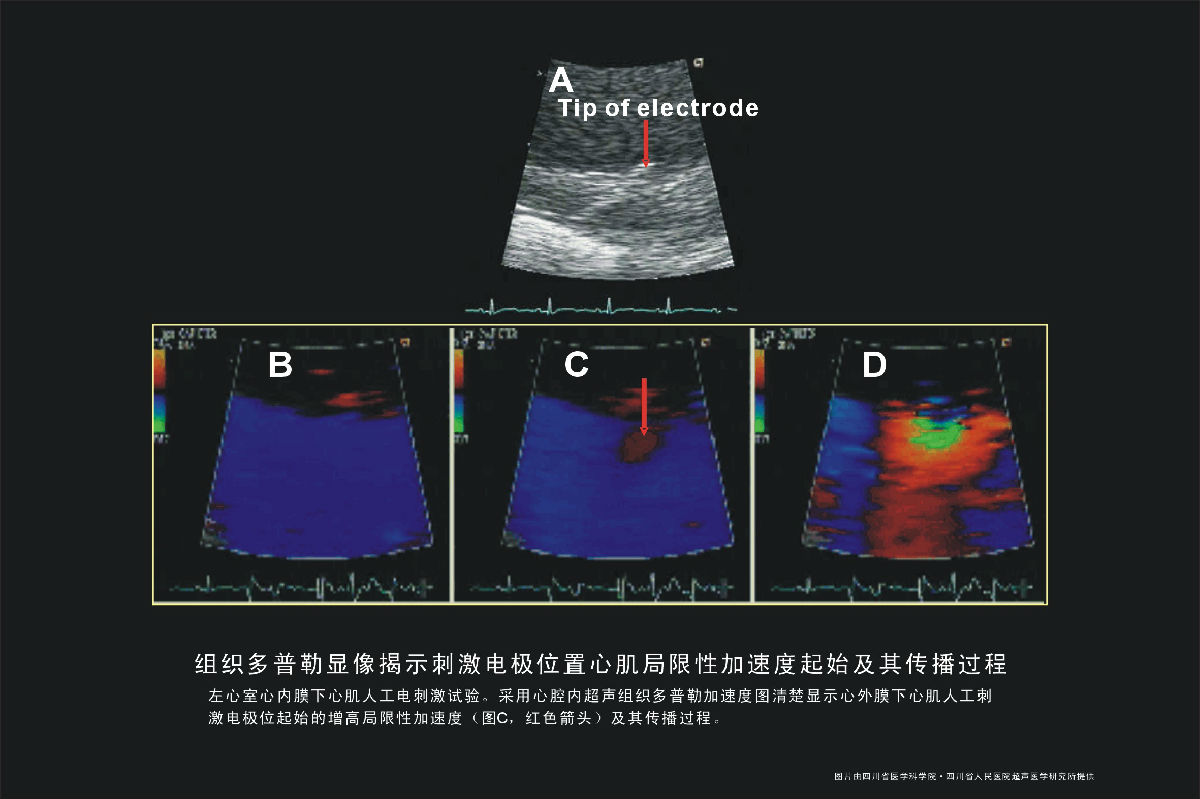

• 电极位置心肌局限性加速

电极位置心肌局限性加速